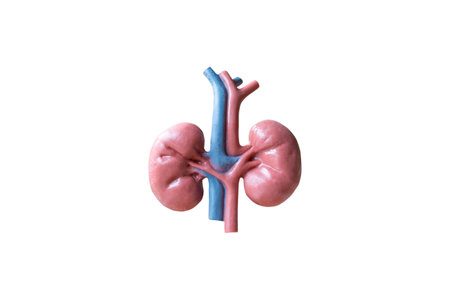

Human Kidneys Anatomical Model isolated on white background

Human Kidneys Anatomical Model isolated on white background